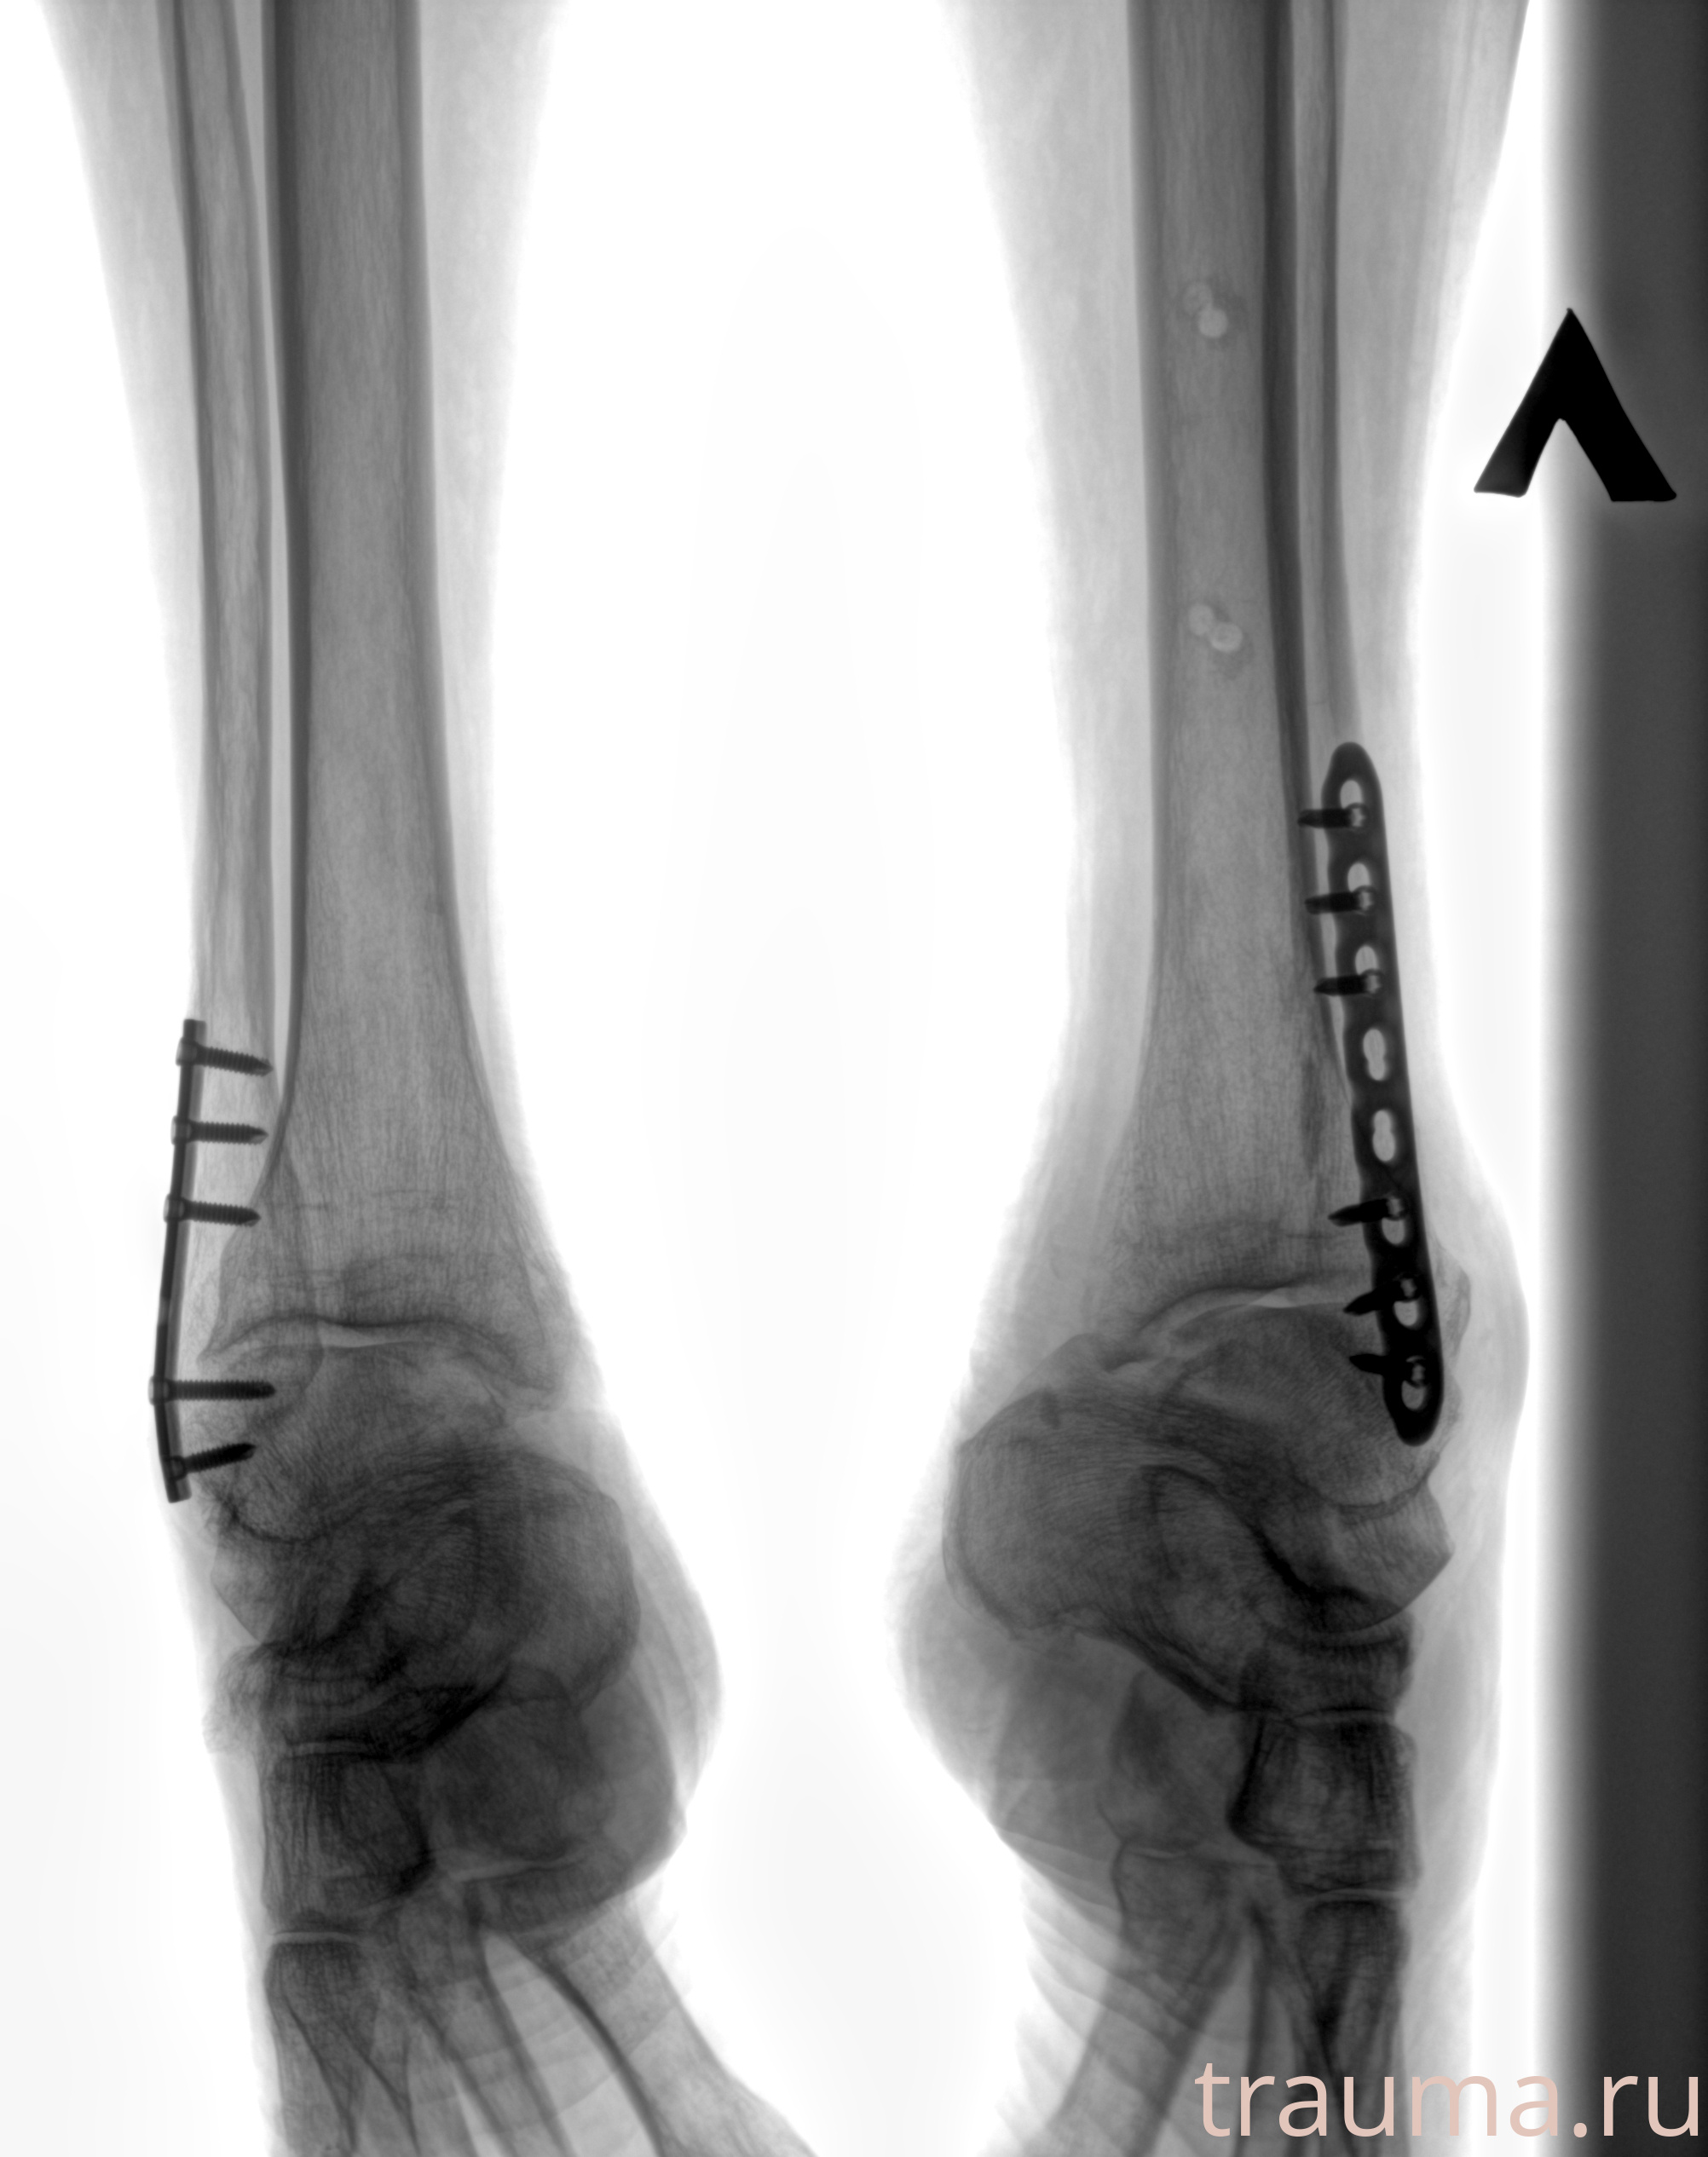

Рентгенограммы